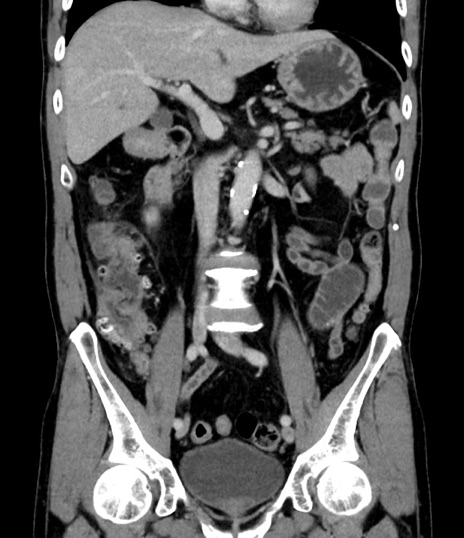

症例8(冠状断像)

【症例】 60歳代男性

【主訴】 黒色吐物

【現病歴】 4日前から嘔気自覚、2日前の朝食後にも嘔気あり、自分で手で嘔吐反射起こし嘔吐したところ血が混ざっていたため受診。

【既往歴】 5年前汎発性腹膜炎を伴う急性虫垂炎で手術、高血圧、前立腺肥大症、高脂血症

【身体所見】 腹部正中に手術癩痕あり 腹部平坦・軟圧痛なし膨満感あり

【データ】WBC 8400、CRP 4.54